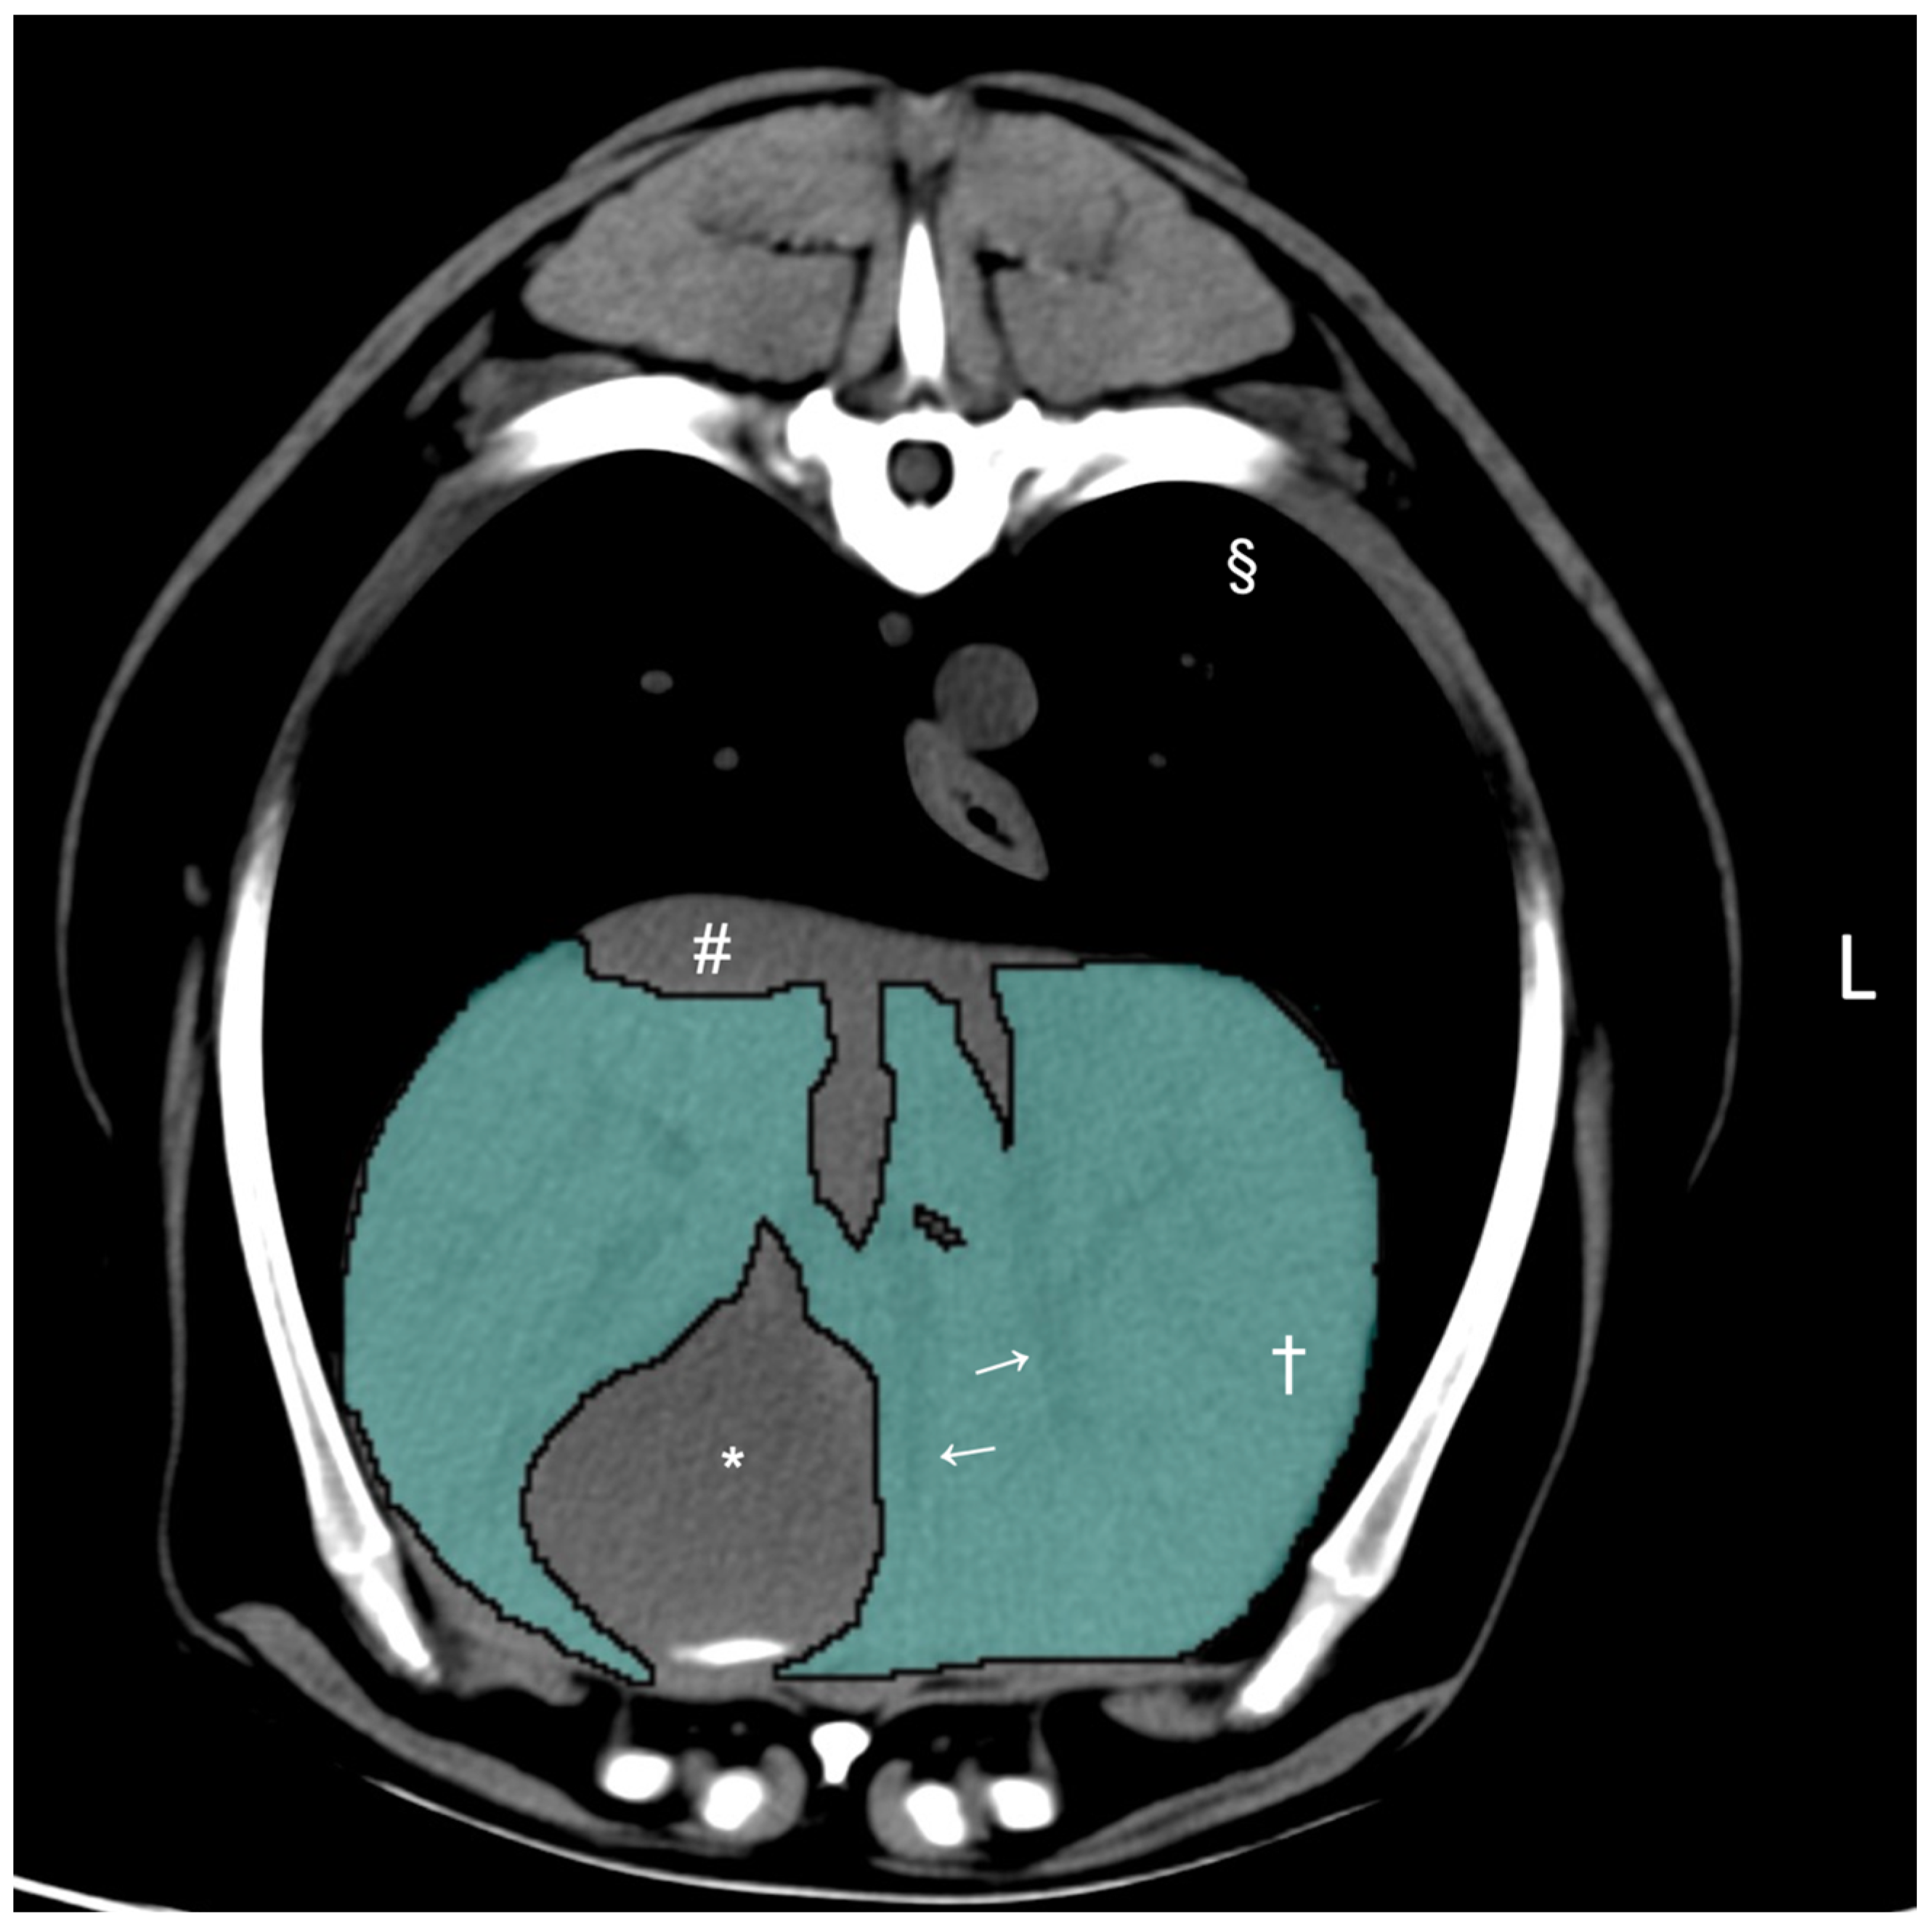

2.2. Computed Tomographic Hepatic Volumetry